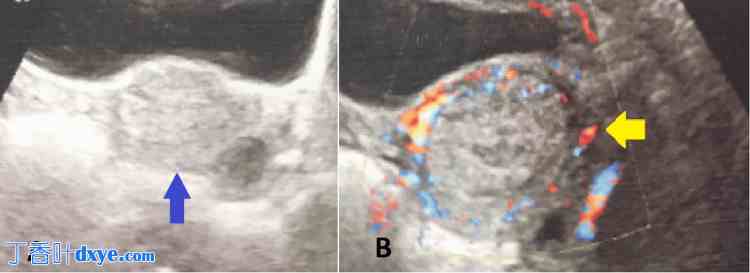

她的血红蛋白为6.2 g/dL。超声检查显示残留胎盘组织(RPOC)大小为3.2 × 3.7 cm,并在子宫内膜腔内发现一个大小为31 × 24 mm的复杂高回声积液。如图2所示,多普勒成像显示周边低回声环和内部血流信号极少,提示为残留胎盘组织(RPOC),未见动静脉畸形。

图2. 超声成像。

(A)蓝色箭头指示子宫内膜腔内一个大小为31 × 24 mm的复杂高回声积液。

(B)黄色箭头指示多普勒成像显示的周边低回声环和内部血流信号极少。